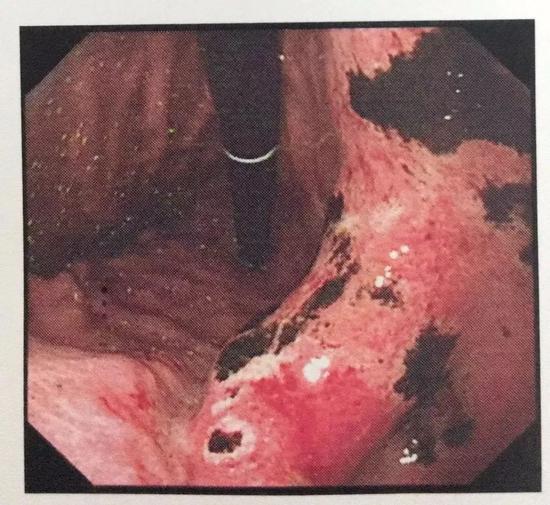

在无痛胃镜下,清晰显示小张整个胃部满布大片状糜烂和出血病变,还有很多溃疡形成的黑痂附着,为急性胃黏膜病变,损伤程度较重。